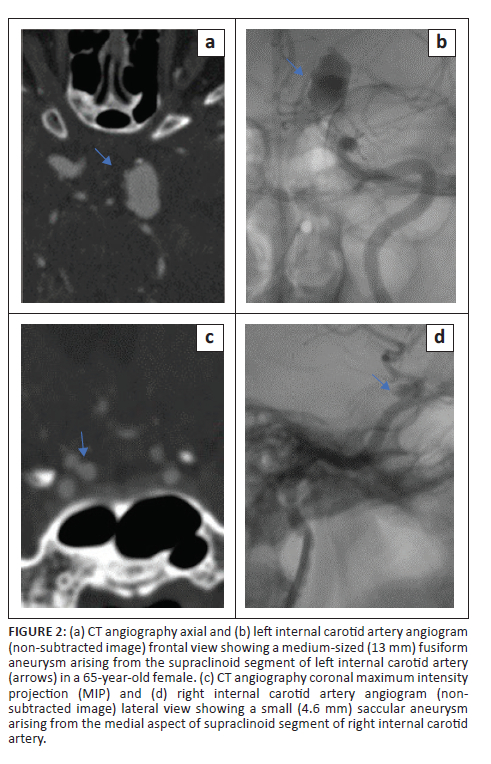

Statistical analysis regarding aneurysm size and location was performed on per patient-basis, which was 94 aneurysms considered to be ruptured in 94 patients. The aneurysm size ranged from 1 mm to 30 mm, with a median of 5.8 mm (IQR: 4.0-8.3). The frequency distribution of aneurysms by size group as determined by DSA and the respective CTA detection efficiency are demonstrated in Table 3. The large and giant aneurysms were all correctly identified on CTA; however, they were very few in number (6/94), therefore, were excluded from comparative statistical analysis. Computed tomography angiography missed 7 of 10 (70%) very small aneurysms (< 3 mm) resulting in a poor sensitivity of 30%. The CTA sensitivity (30%) for very small aneurysms (< 3 mm) was significantly poor compared with the 3-5 mm (small size) group, the > 5 mm to < 15 mm (medium-sized) group and the overall CTA sensitivity (80%) (p = 0.024). Figure 1 shows a very small and a small aneurysm.

Diminished CTA sensitivity for very small aneurysms (≤ 3 mm) is well documented in the literature,11,15,17 which is congruent to this study. In contrast Lu et al. demonstrated good CTA sensitivity even for aneurysms < 3 mm in size using dual energy CTA.12 Some authors reported no difference in CTA sensitivity for anterior versus posterior circulation aneurysms.11,12 This finding is supported by this study, even though the aneurysm frequency proportions were markedly skewed towards the anterior circulation. Several studies reported lower CTA sensitivity for locations close to the bony base of skull such as the ICA14,15 and PComm.19 The latter was congruent with the findings of this study, which demonstrated significantly lower PComm sensitivity (56%) compared with other major anterior circulation locations. The ICA location however did not show significantly compromised CTA sensitivity in this study (Figure 2).